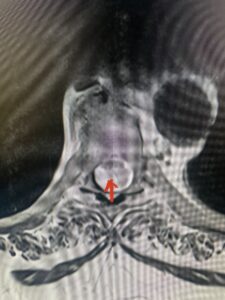

This 47-year-old male who four months prior was lifting weights developed sharp pain in his neck. After that he developed progressive numbness in his arms, neck pain and headache. He said that the right arm was worse than the left. On examination the patient had long tract weakness on the right side which included his triceps, finger extensors, hip flexors, and dorsiflexors. The patient did not have hyperreflexia. MRI (Fig. 2) demonstrated a massive, extruded disc herniation with severe cord compression. The patient because of progressive myelopathy and spinal cord compression was indicated for anterior cervical discectomy and fusion at C4-5 (Fig. 3). Patient had significant improvement of weakness and numbness post operatively.

Fig. 2a Sagittal T2-weighted cervical MRI demonstrating large C4-5 herniated disc with spinal cord compression (red arrow)